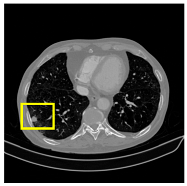

3.4.2. Representative Cases with Segmentation Challenges on the MEF-PN35 Dataset

To complement the quantitative evaluation, we present a set of representative cases from the clinical dataset that exhibited typical segmentation challenges. These cases were selected to reflect diverse morphological characteristics observed in pulmonary nodules, such as spiculated boundaries, small size, vessel adherence, pleural attachment, cavitation, and clear isolation. Rather than aiming for exhaustive categorization, our intent is to highlight a range of practical difficulties encountered in real-world scenarios and to qualitatively assess how different boundary-aware loss functions respond to these variations. Each challenge is labeled (C1) through (C5) in Table 10 and is consistently referenced in the corresponding detailed illustrations that follow.

Following the summary in Table 11, we present detailed visual comparisons for selected representative cases, each corresponding to a specific segmentation challenge. These cases are consistently labeled using the Challenge ID (CID) codes defined in Table 9 to facilitate cross-referencing between the summary and the case illustrations. Each table reports segmentation results across three loss configurations (Sobel, Laplacian, and Hausdorff) using five columns. Loss indicates the boundary loss formulation applied in each case, where Dice loss is combined with a boundary term computed using Sobel, Laplacian, or Hausdorff operators. The Segmentation Result column shows four images side by side: the input CT patch, the manual ground truth, the model prediction, and a color-coded difference map between ground truth and prediction. In this map, green indicates true positives, blue represents true negatives, red corresponds to false positives, and yellow denotes false negatives. The final column, Attention Map, presents Grad-CAM visualizations derived from one of the Adaptive Attention Fusion (AAF) layers in the encoder path. These maps illustrate the spatial focus of the model, with red/yellow regions indicating strong attention and lighter or neutral tones indicating lower activation. All six cases are presented in detail in Table 11, Table 12 and Table 13, providing a comprehensive qualitative analysis of how each loss configuration performs under specific segmentation challenges observed in real clinical data.